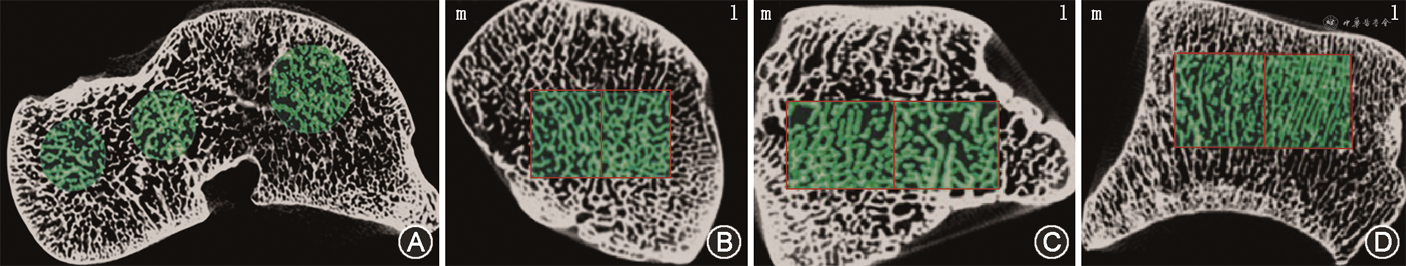

为研究距骨内骨小梁结构,使用硬组织切片机(德国艾卡特公司E300CP型)分别在冠状面、矢状面及水平面将距骨切成2 mm厚的薄骨片,随后使用超高分辨X线成像系统(美国Faxitron公司)对切片进行扫描,扫描电压10~100 kV,电流0.3 mA(图1),对所得冠状位、矢状位及水平位X线片距骨头、颈、体小梁走行、疏密、结构进行大体描述。在进行组织切片前,对全部距骨使用德国Siemens公司InveonTM系统的Micro-CT机器进行扫描并三维重建,扫描电压80 kV,电流500 μA,扫描分辨率为36.12 μm(中分辨率),分别计算距骨头、颈、体的骨体积分数(BV/TV,%)、骨表面积分数(BS/BV,mm-1)、骨小梁厚度(Tb.Th,μm)、骨小梁数目(Tb.N,mm-1)、骨小梁间距(Tb.Sp,μm)及骨小梁模式因子(TPF,mm-1),分别对相同侧别不同部位以及相同部位不同侧别的各项参数的差异进行比较(图2)。

Micro-CT扫描发现距骨头、颈、体内外侧骨小梁BV/TV、Tb.Th、Tb.N、Tb.Sp以及TPF等参数并无差异,故将头、颈、体内外侧小梁作为整体计算分析,发现距骨左右侧的相同部位小梁呈对称分布,无明显差异。相较于头、颈骨小梁,体部骨小梁以板状小梁为主,小梁数量更多、间距更小、排布更为致密,连续性更好,头颈骨小梁以杆状骨小梁为主。然而本研究仍有一定的局限性:由于标本获取较为困难,标本数量仍较少;年龄分组不全面,无法研究骨内结构与年龄的相关性。